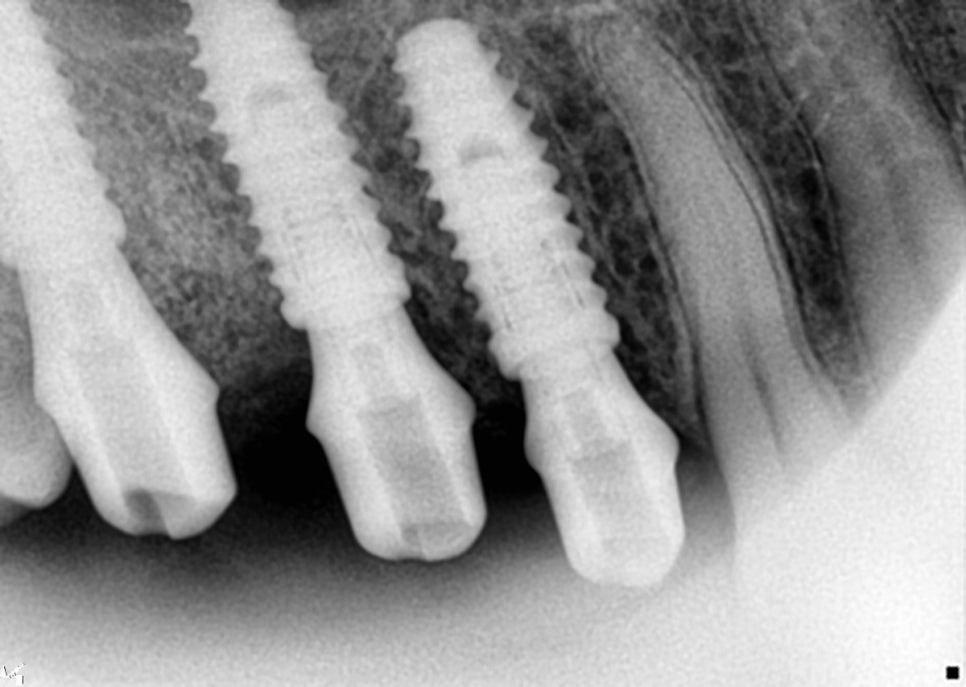

상악동 거상술을 시행한 부분을 보면

오른쪽 위 첫번째와 두번째 큰 어금니 부위는

크레스탈 접근법(crestal approach)을

이용한 상악동 거상술을 진행했습니다.

위쪽 3개 임플란트 식립 완료

임플란트 식립하는 구멍을 통해 상악동막을

거상을 하는 방식인데요.

매우 정밀하게 진행을 해야합니다.

측방 접근법에 비해서는 침습자체가 적고

회복이 빠르다는 장점이 있습니다.

각 임플란트 부위마다 적절한 골이식재를

사용했고 인접 치아의 장축과 평행하게

정확한 각도로 식립하는 것이 중요하거든요.

초기에 고정력도 다행히도 양호하게

진행이 된 편이라 힐링 어버트먼트를

장착한 채로 골유착을 기다리기로

환자분에게 말씀드렸습니다.